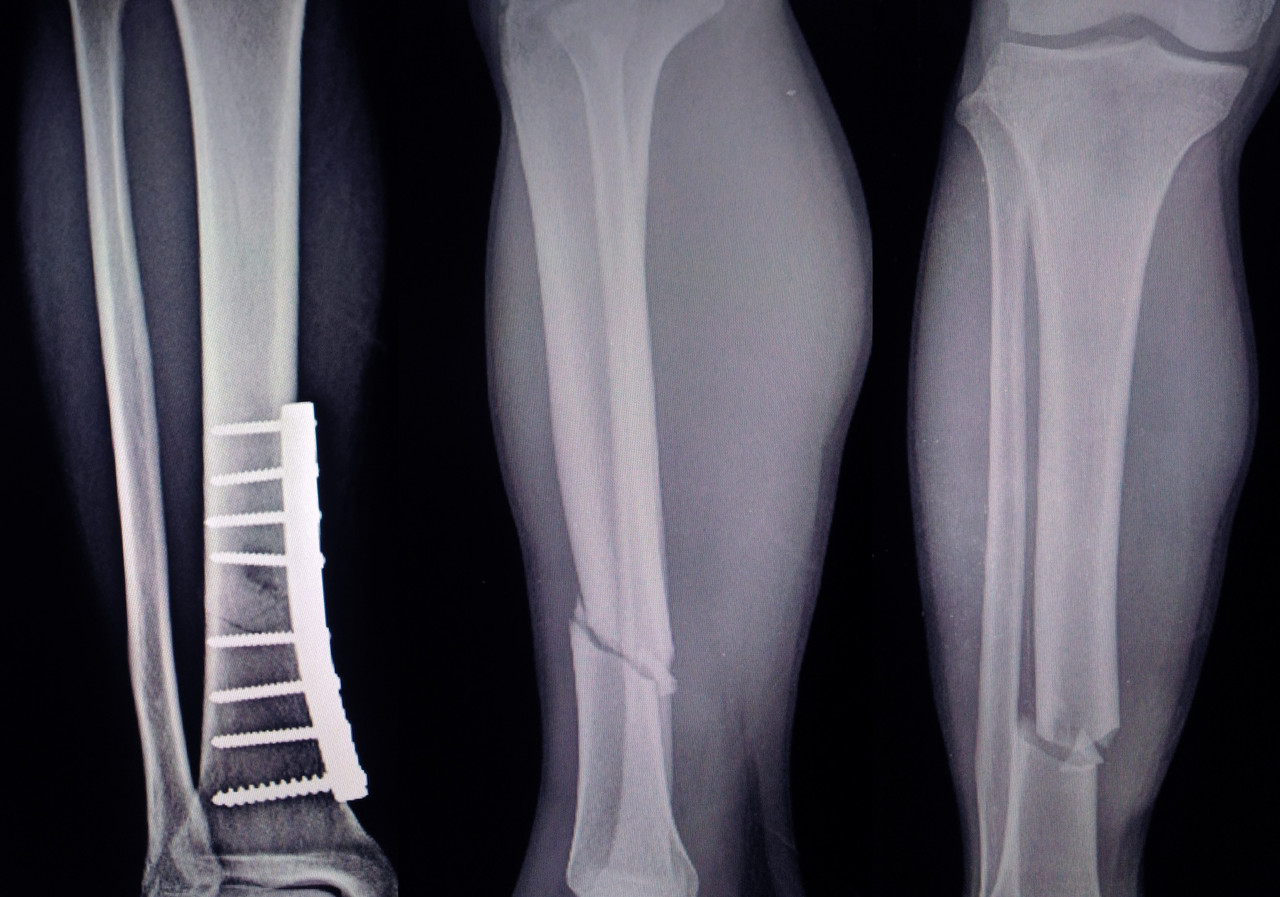

유합은 골절 후 뼈가 붙은 상태를 의미합니다. 부정 유합은 뼈가 제 위치에 붙지 않은 상태를 의미합니다. 불유합은 뼈가 붙지 않은 상태로 골절 부분의 치유 과정이 보이지 않는 상태를 의미합니다. 불유합의 경우 골절선이 계속 보이거나 골절 끝 부위에 경화가 확인됩니다.

또한 가골 형성이 비대하거나 없기도 합니다. 가골이란 뼈가 부러진 후 붙는 과정에서 생기는 정상적인 뼈 조직으로, 가골이 형성되어 뼈들이 붙으면 정상적인 뼈가 됩니다. 자연적으로는 골절 유합이 일어나지 않으며, 골 이식이나 재수술 같은 정형외과적 처치가 필요합니다.

✅ 불유합 증상

골절된 사지에 국소 종창이나 발적이 생길 수 있습니다. 움직이거나 부분적인 체중 부하가 발생하면 통증이 생깁니다. 골절부의 움직임을 보일 수 있습니다. 불유합이 오래 지속되면 해당 부위에 가관절증(Pseudoarthrosis)이 형성되기도 합니다.

2. 불유합 치료

불유합 치료의 목적은 통증을 제거하는 것, 골 경화를 통해 정렬을 회복하는 것, 손상된 사지의 기능을 회복하는 것입니다. 치료 방법은 비수술적 방법과 수술적 방법으로 나눌 수 있습니다. 환자 개개인에 맞는 치료 방법을 선택해야 합니다.

※ 비수술적 방법 : 석고 및 보조기 고정, 전기 자극, 초음파, 골수 주사법

※ 수술적 방법 : 박피술, 자가골 이식술, 가골 신연술, 유리 혈관부착골 이식술, 동종골 이식술, 골이식 대체술, 금속판 고정술, 골수강 내 고정술, 외고정장치 고정술